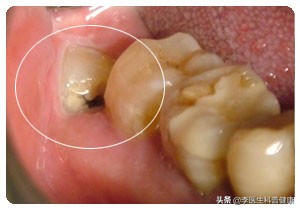

2、侵犯邻牙,清洁不易

智齿萌发的空间不足,会倒在第二磨牙上,因而造成第二磨牙清洁不易,甚至将前面的好牙顶坏,继而出现龋齿、牙齿松动的症状。